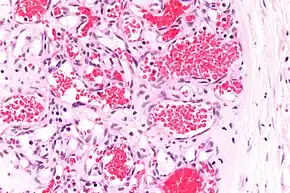

A precise history of the growth characteristics of the IH can be very helpful in making the diagnosis. In the first 4 to 8 weeks of life, IHs grow rapidly with primarily volumetric rather than radial growth. This is usually followed by a period of slower growth that can last 6–9 months, with 80% of the growth completed by 3 months. Finally, IHs involute over a period of years.[24] The exceptions to these growth characteristics include minimally proliferative His, which do not substantially proliferate[23] and large, deep IHs in which noticeable growth starts later and lasts longer.[24] If the diagnosis is not clear based on physical examination and growth history (most often in deep hemangiomas with little cutaneous involvement), then either imaging or histopathology can help confirm the diagnosis.[21][25] On Doppler ultrasound, an IH in the proliferative phase appears as a high-flow, soft-tissue mass usually without direct arteriovenous shunting. On MRI, IHs show a well-circumscribed lesion with intermediate and increased signal intensity on T1- and T2-weighted sequences, respectively, and strong enhancement after gadolinium injections, with fast-flow vessels.[21] Tissue for diagnosis can be obtained via fine-needle aspiration, skin biopsy, or excisional biopsy.[26] Under the microscope, IHs are unencapsulated aggregates of closely packed, thin-walled capillaries, usually with endothelial lining. Blood-filled vessels are separated by scant connective tissue. Their lumina may be thrombosed and organized. Hemosiderin pigment deposition due to vessel rupture may be observed.[27] The GLUT-1 histochemical marker can be helpful in distinguishing IHs from other items on the differential diagnosis, such as vascular malformations.[22]